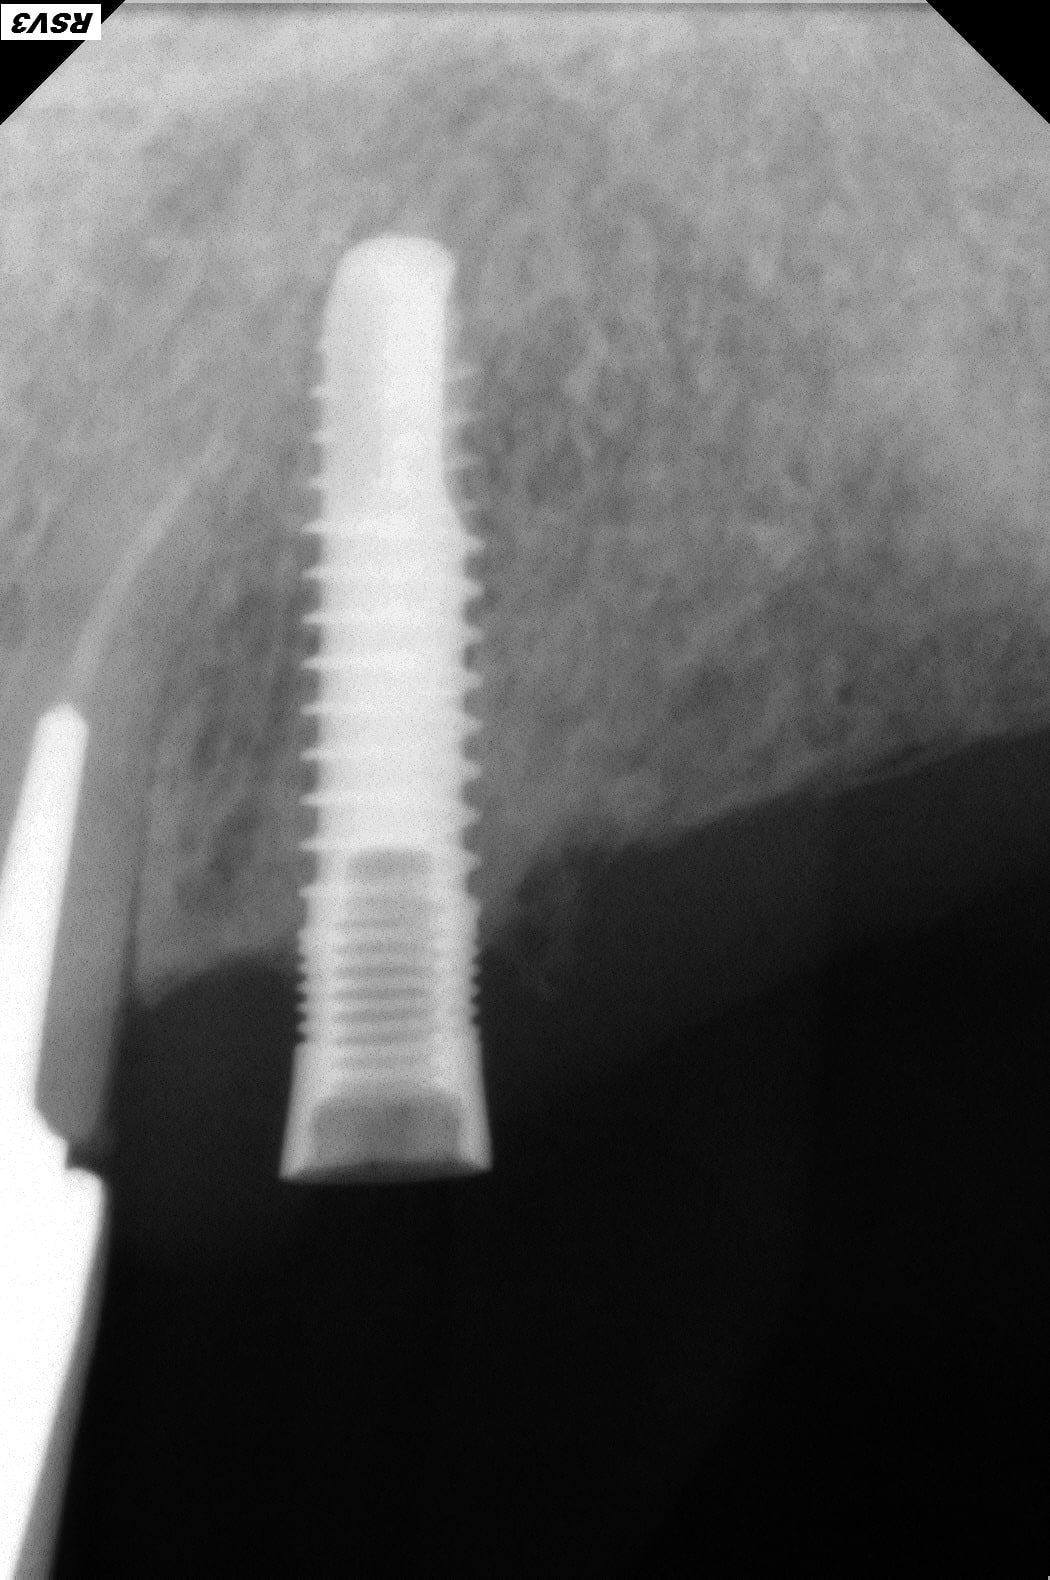

Patient 85 ans vient avec un bridge implanto porté dans sa main

C'est 2 implants Global D EVL (ex Serf), le premier est de diamètre 3.3 et la second (plus court) est un diamètre 4. Sur le système prothétique angulé du diamètre 4 on remarque la présence d'un anneau esthétique. Que souhaitez-vous faire ?

il est conseillé de remplacer les vis respectivement ref.DVPEG3.3 et DVPEG4ET5AA (celle du Ø4 qui est sur la photo n'est pas la bonne vis), le tournevis doit être avec un hexa de 1.2 mm et le couple de serrage de 35 N.cm (Global D prête le kit si besoin). Dans le cas du diamètre 4, effectuer un 1er serrage pour "impacter" l'anneau esthétique, desserrer et resserrer au couple. Bien vérifier que tous les composants sont bien jointifs avant de sceller le bridge.

Après réflexion j'ai l'impression qu'il n'y a pas que la vis qui ne va pas sur le Ø4, il y aurait aussi le FM angulé, est-il a fond en buté dans l'anneau esthétique? en théorie la hauteur de l'hexagone ne devrait pas excéder 1 mm, s'il est aussi haut que celui de l'anneau, c'est qu'il est prévu pour ce monter sans l'anneau (donc dans ce cas la vis correspondrait). Bien vérifier aussi le filetage dans l'implant en demandant un taraud de nettoyage ref. DKREEVLM2 (en prêt si possible), ce type d'assemblage non adapté peut entrainer des dévissages récurrents qui amènent parfois le praticien à utiliser un produit frein filet.